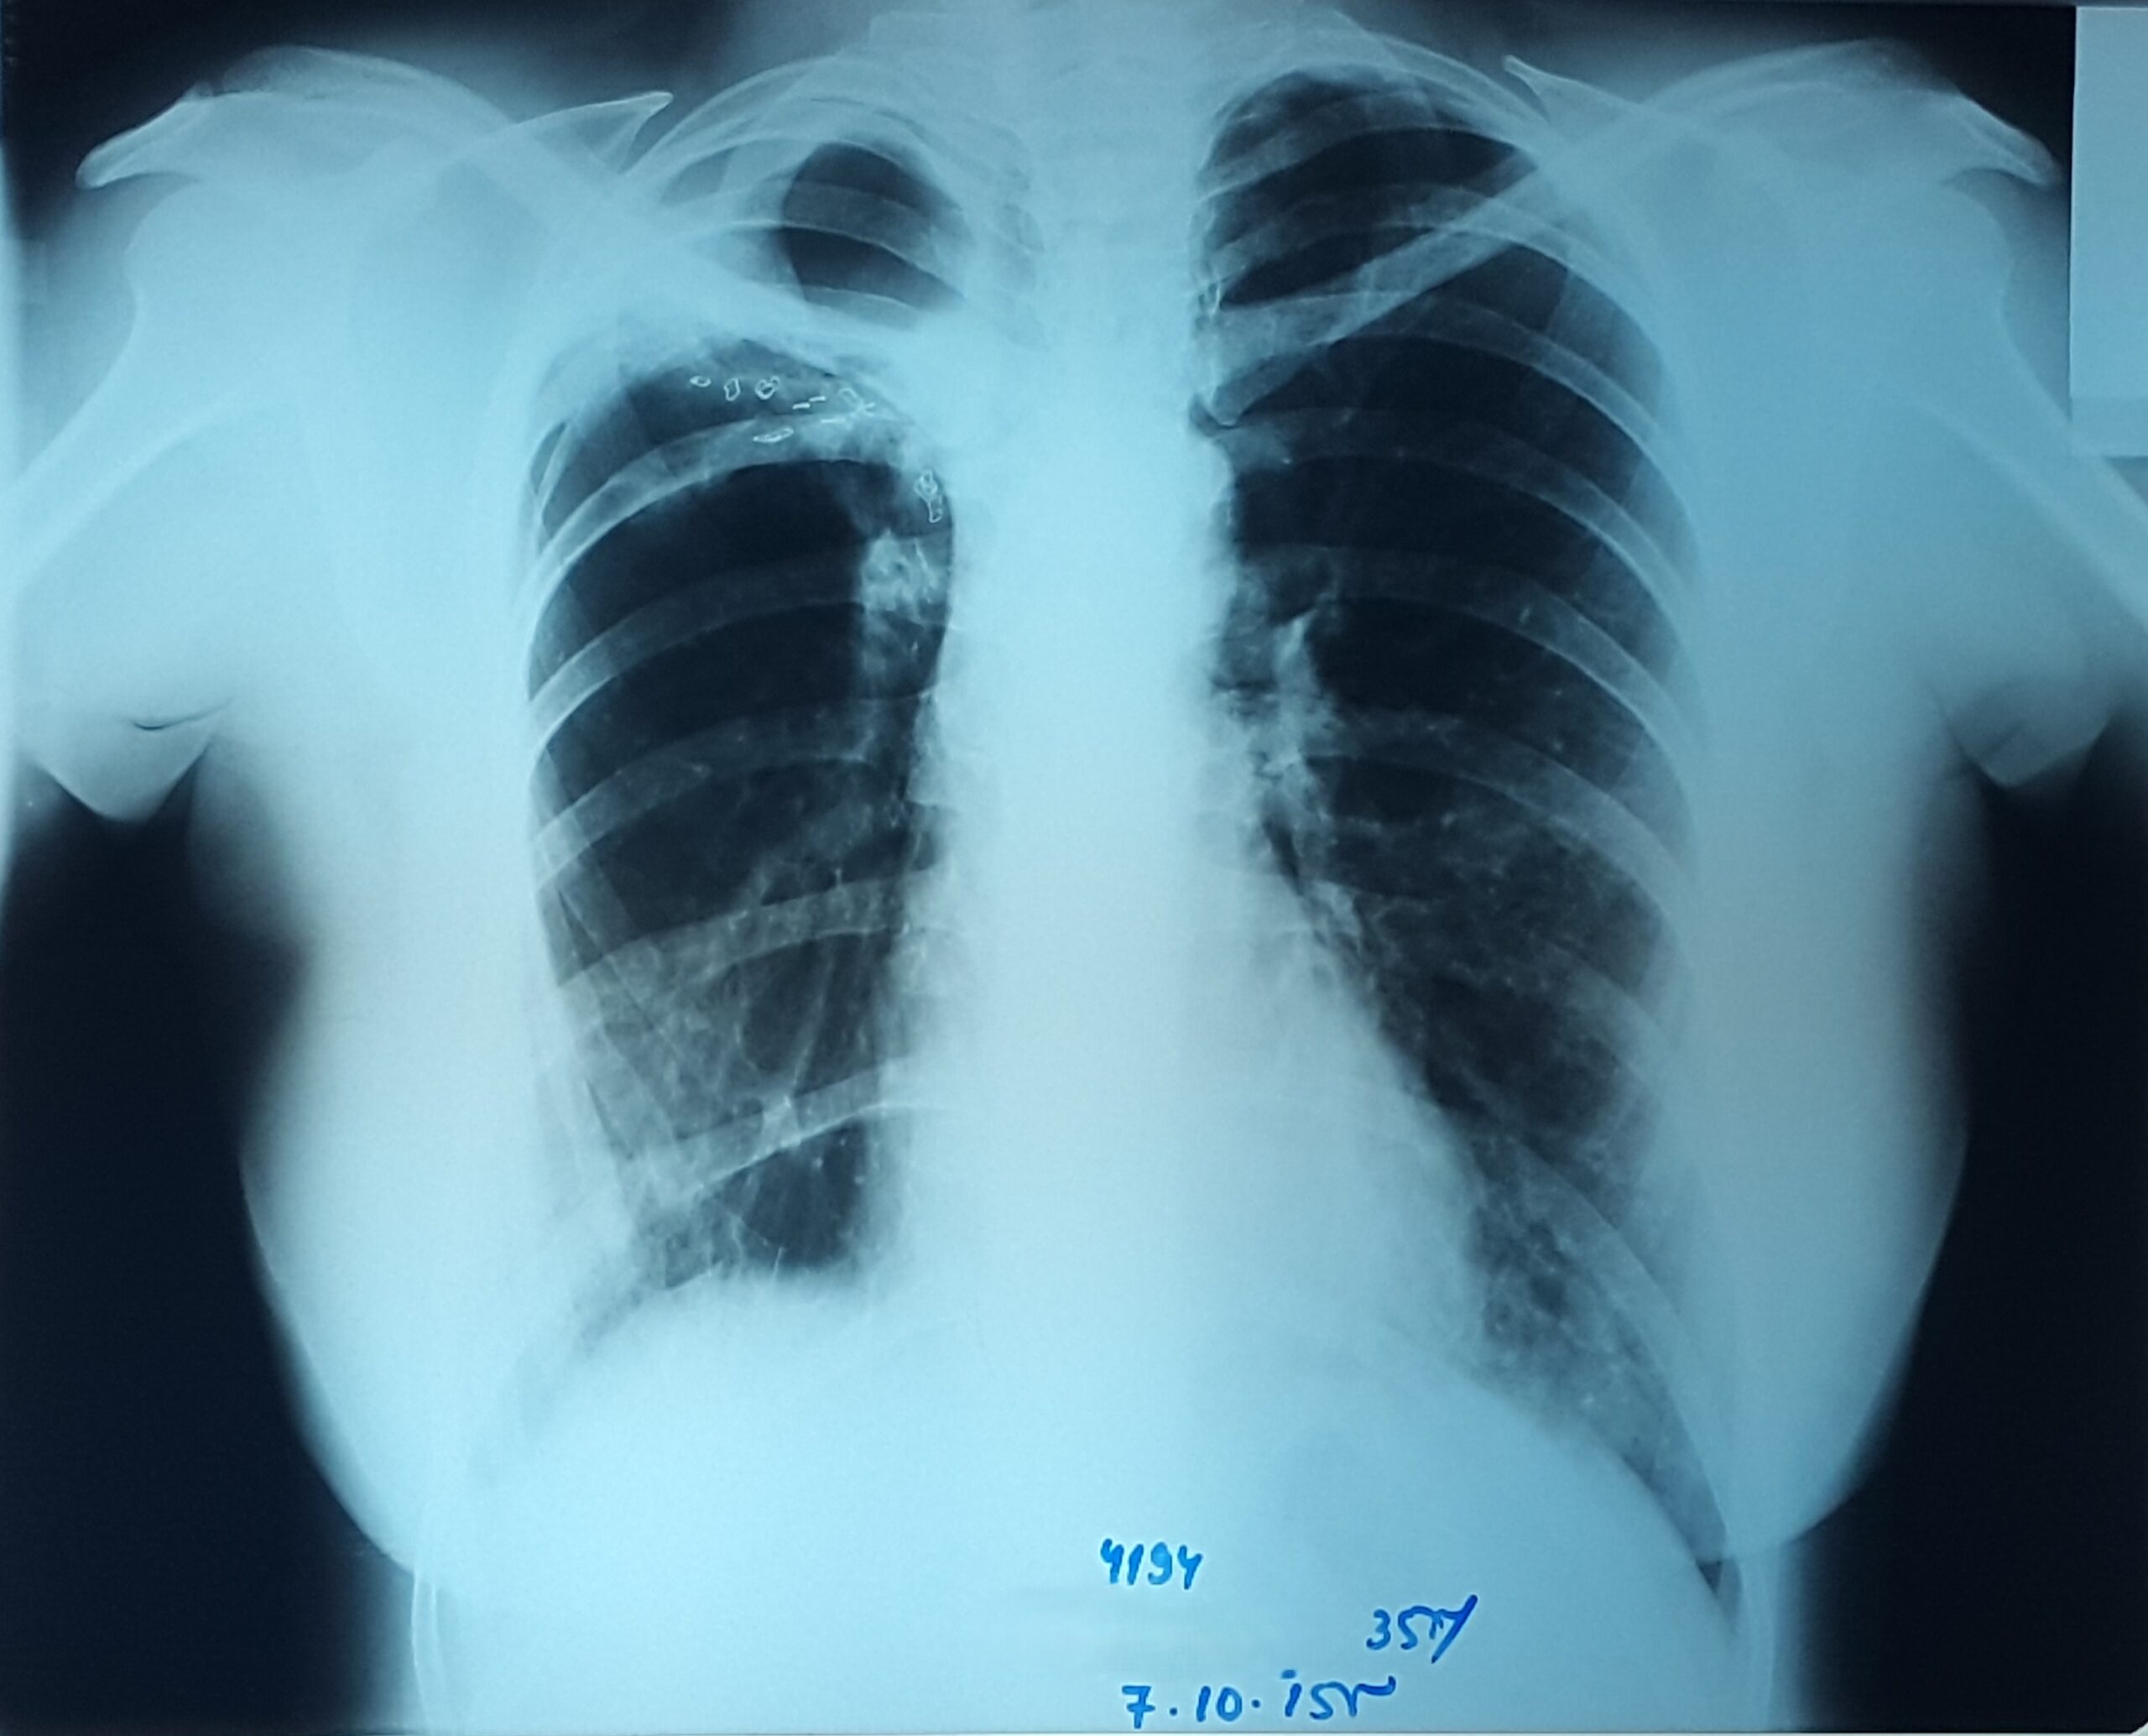

პაციენტი 37 წლის ქალი. 1997 წ-ს გაკეთებული აქვს მარჯვენა ზედა წილის რეზექცია ფილტვის ტუბერკულოზის გამო. წლების განმავლობაში აქვს გამწვავებები, რაც გამოიხატება მაღალი ცხელებით, ხველით, დიდი რაოდენობით სისხლნარევი, მძაფრი სუნის მქონე ნახველის გამოყოფით. რენტგენოლოგიურად ინახა დიდი ზომის ღრუ მარჯვენა ფილტვის ზედა ველში. ბრონქოსკოპიით ინახა დიდი ზომის მარჯვენა ზ/წილოვანი ბრონქის ტაკვის ფისტულა. ტაკვის სიგრძე იძლეოდა ბლოკატორის ჩადგმის შესაძლებლობას. რიგიდული ბრონქოსკოპით მარჯვენა ზ/წილოვან ბრონქში ჩაიდგა MEDLUNG-ის ბლოკატორი N13. რამოდენიმე საათში საჭირო გახდა ბლოკატორის გამოცვლა ნაკლებ (N12) ზომაზე განვითარებული მარჯვენა ქვედა წილის ატელექტაზის გამო. მანიპულაციის შემდეგ პაციენტს შეუწყდა სისხლნარევი და ჩირქოვანი სეკრეტი. 10 თვის შემდეგ საკონტროლო გამოკვლევით ღრუს ადგილას დაფიქსირდა ფიბროთორაქსი. უახლოეს მომავალში, გულმკერდის კტ კვლევის შემდეგ, იგეგმება ბლოკატორის ამოღება.